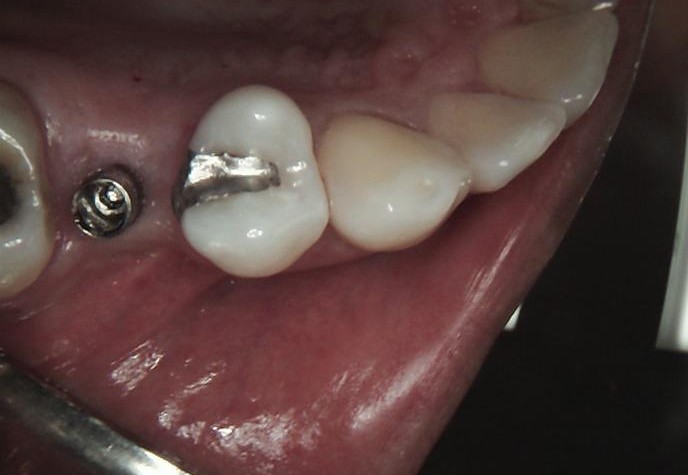

A healing cap was placed to guide soft-tissue contouring and support optimal formation of the emergence profile.

FINAL

After successful osseointegration, the definitive restoration was delivered using a Ti-base-supported crown, held by Dr Carmy.

Final radiographic evaluation confirmed proper implant positioning and bone stability.

The treatment resulted in a functional, stable, and esthetically harmonious restoration fully integrated with the adjacent dentition.